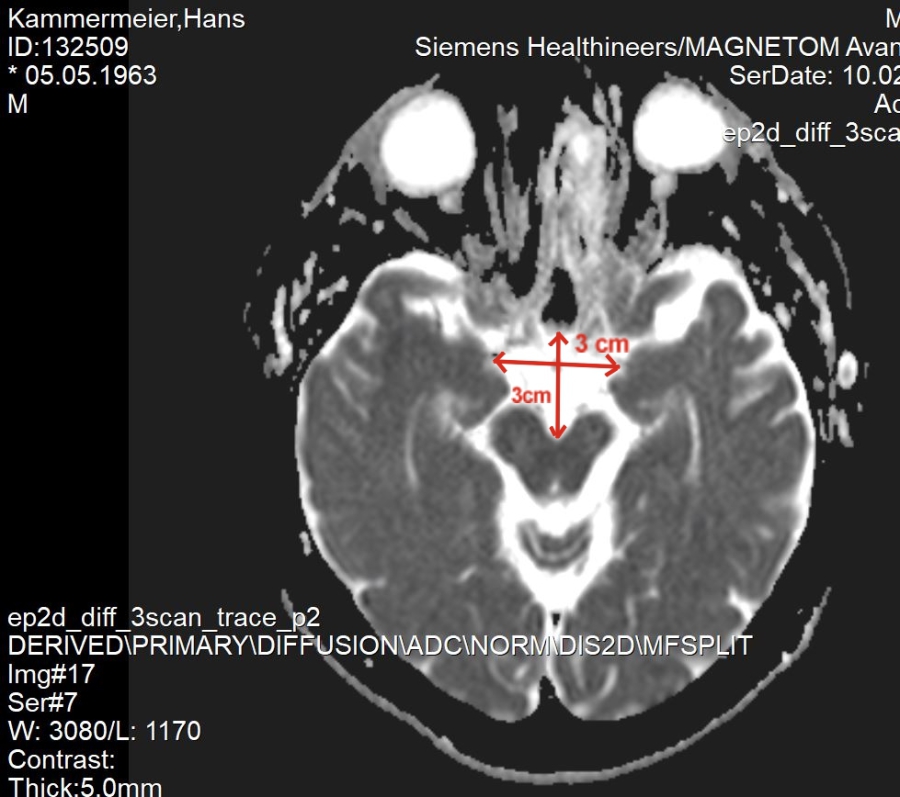

Am 16.05.2016 (Pfingstmonatg) habe ich mit 53 Jahren um 12:30 Uhr einen Schlaganfall auf der rechten Seite erhalten. "Links war der Adern Verschluss."

Ich habe einen Riss in der Halsschlagader gehabt, dann hat sich ein Blutbatzen gebildet und ist dann rauf in meinem Kopf!

Zufallsbefund, muss jedes Jahr überprüft werden!